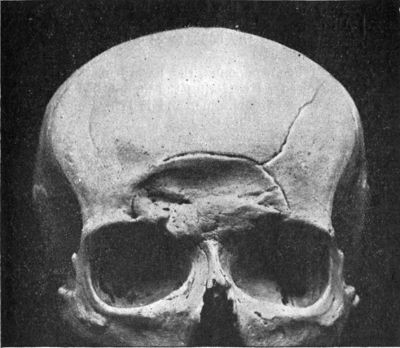

354 188.Depressed Fracture of Frontal Bones with Fissured Fracture

365 189.Depressed and Comminuted Fracture of Right Parietal Bone: Pond Fracture

365190.

Pond Fracture of Left Frontal Bone, produced during Delivery